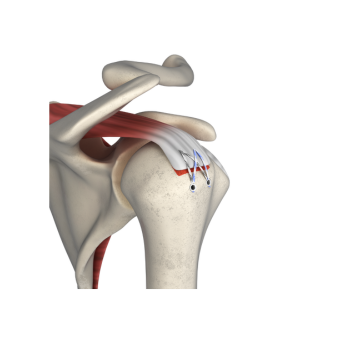

fThis technique features knotless fixation of the rotator cuff using 2 pcs of PEEK Suture Anchors (for medial row) with Fiber Tape and 2 pcs of PEEK Knotless anchors (for lateral row). Knotless PEEK Suture Anchor is available in diameter of 4.75 and 5.5mm with 1 pc of locking Fiber Tape and 1 pc of Fiber Wire. The anchor is inserted in the medial row of the rotator cuff. These Fiber Tapes are passed through the cuff tissue and then loaded into Knotless PEEK Suture Anchor and it is fixed on the lateral row using knotless anchor. The technique eliminates the need for multiple suturing passes, reducing post-operative pain and recovery time. It also increases the structural integrity of the repair, ensuring a lasting and secure fix. It is a predural time saving than the regular knot tying repairs.